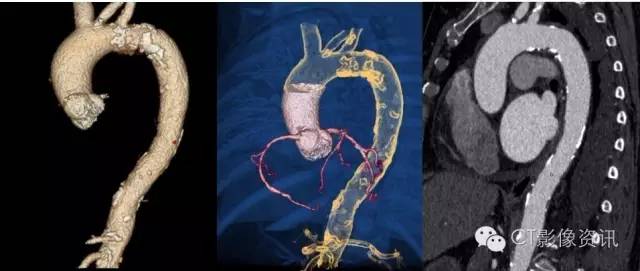

高心率的可以一个心跳扫描完成,那心率不齐,房颤的,以往设备都做不好的能行不?您看,房颤的患者来了!

您看看这心跳的节律,一会儿53,一会儿116,让扫描老师咋办?这种极不规则的心率对常规的设备就是一场惊心动魄的挑战!假如扫描时落在低心率时,成功率比较高;假如扫描时落在高心率时,有可能不成功,假如扫描时不幸落在正在活跃的R波上,那就可能导致重做的风险!假如……,噢,现在不用假如了,我用Revolution CT就行了!

这是高血压多年的患者,血管壁发生了大量的钙化。

同时临床医生也想要了解这个有多年高血压病史的房颤患者的心功能情况和主动脉是否也有硬化,这个时候,机智灵活的Revolution CT发挥了一轴心脏扫描,快速进行螺旋扫描切换的方式,进行了主动脉CTA的检查。这给临床医生提供了非常大的帮助。

EF值为:59.9%

主动脉CTA显示清晰主动脉壁弥漫钙化。